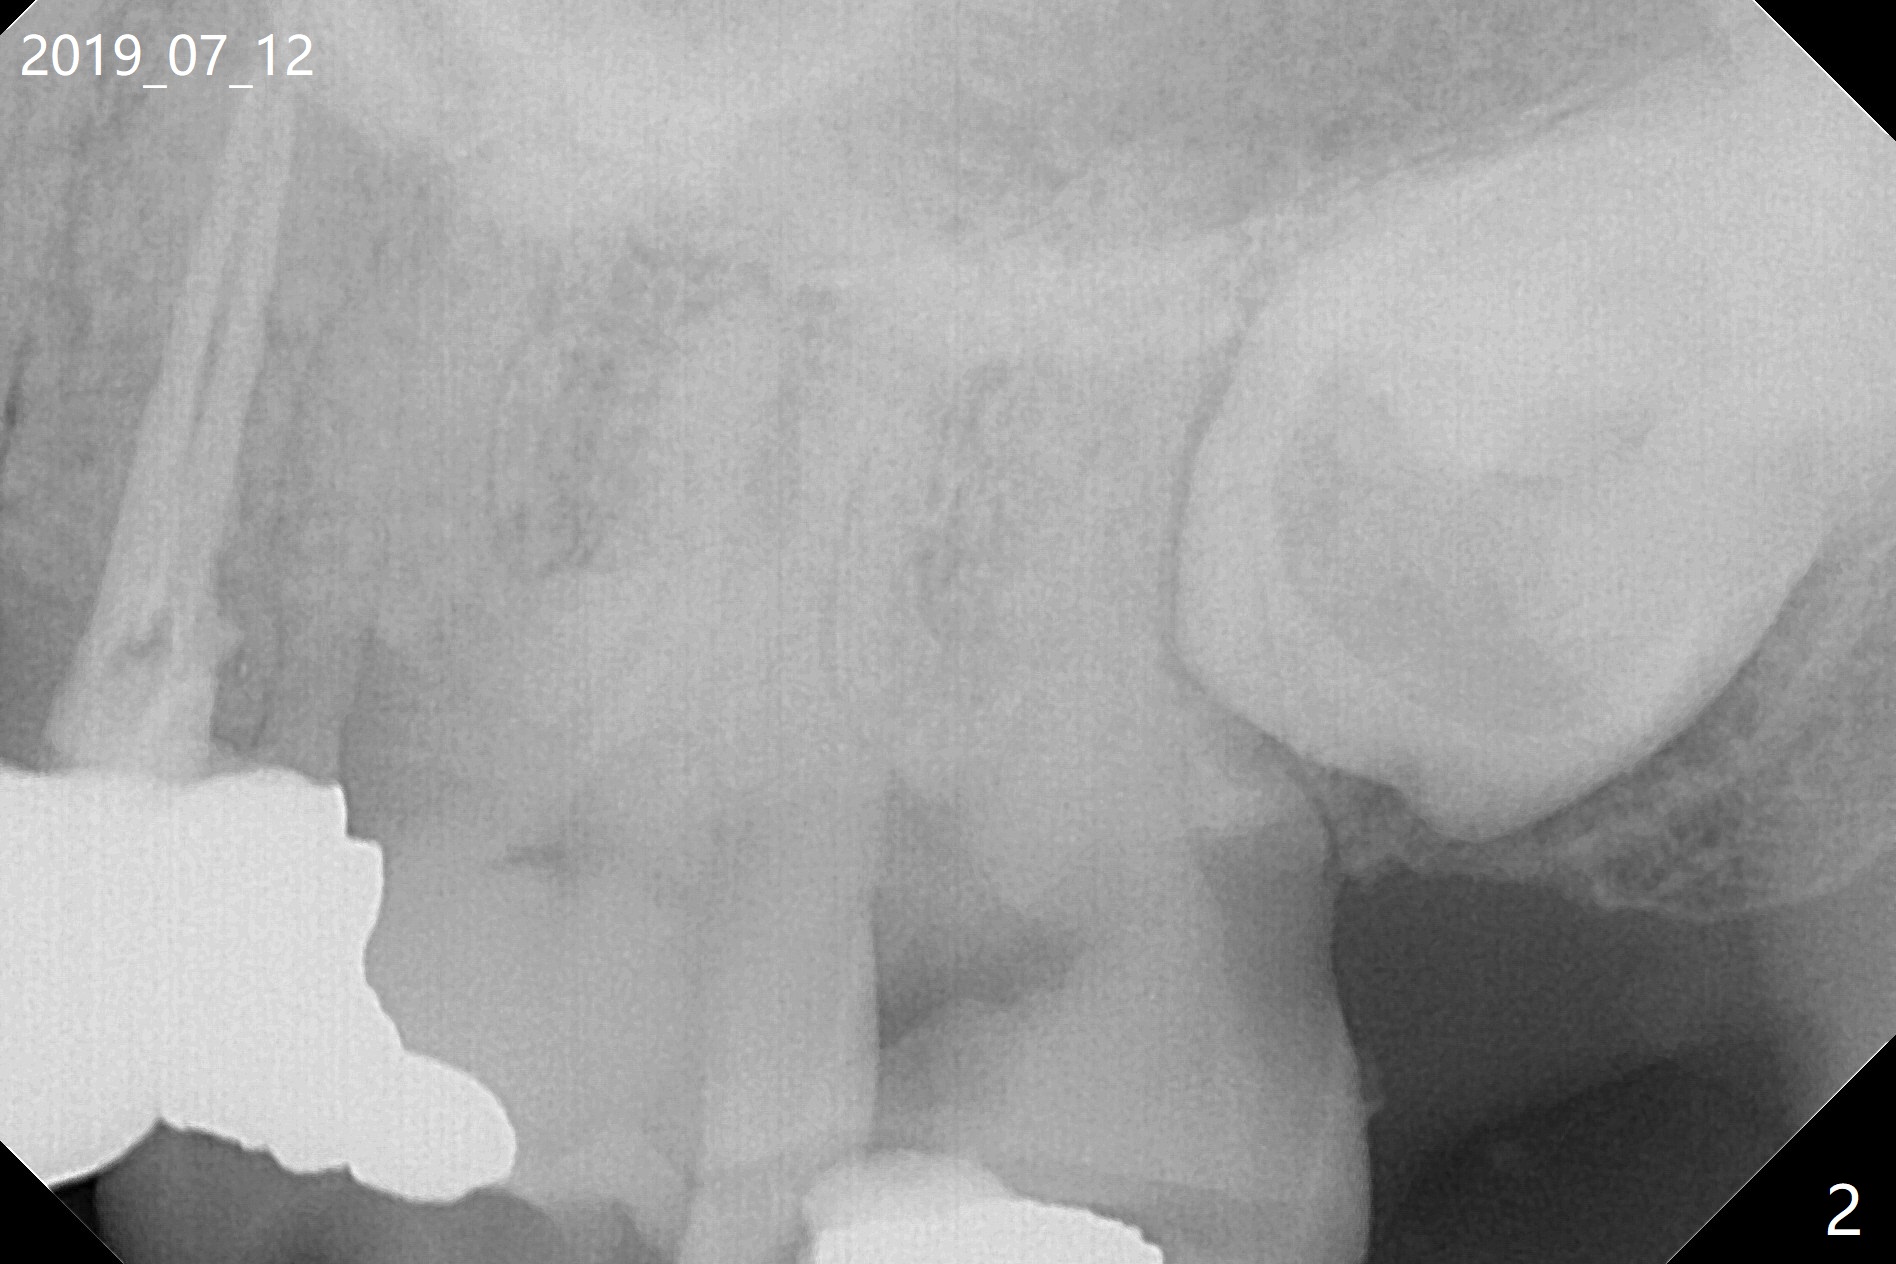

A 62-year-old man returns with acute pulpitis at #15 (Fig.1,2). The caries is confirmed subgingival after debridement. After discussion, the patient agrees with extraction and bone graft, but he does not want to have implant (Fig.3). When he changes his mind, the 3rd molar will be extracted immediately followed by implant placement with guide. Because of the narrow space, the distal surface of the distobuccal root of the 1st molar is exposed when the tooth #15 is extracted. The bone graft will prevent gingival recession of the tooth #14.